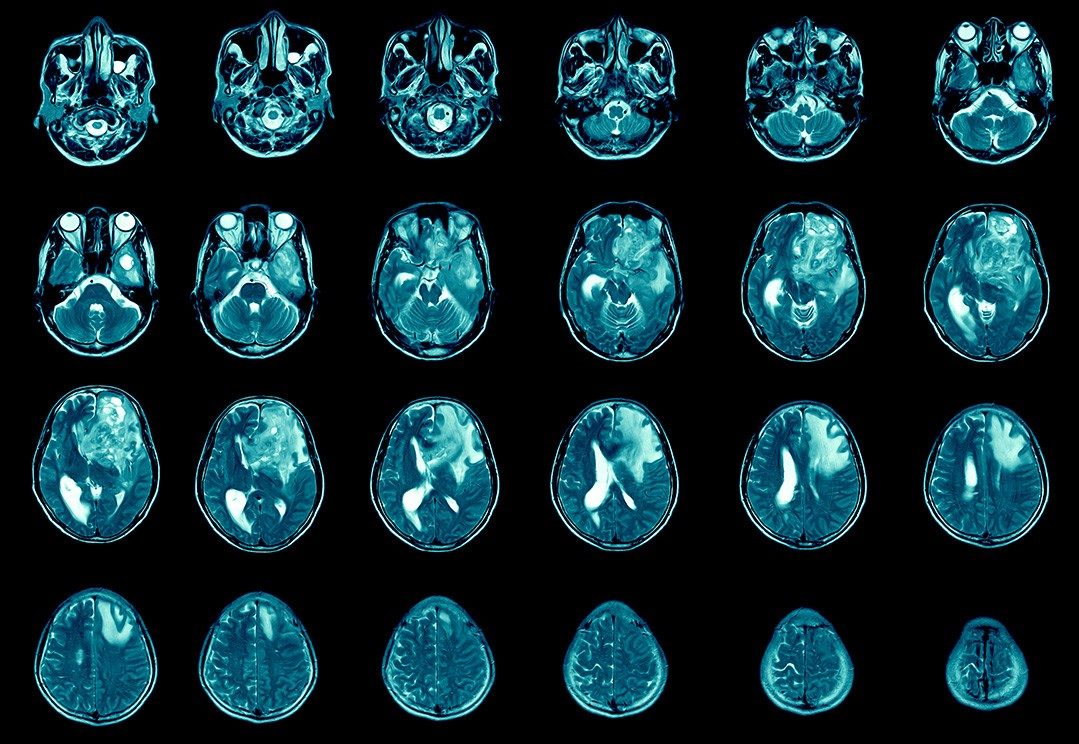

Q&A: Understanding glioblastoma (GBM)

If you’ve been diagnosed with glioblastoma (GBM), you might have questions about treatment options. While glioblastoma is an aggressive tumor, there are many advances and treatment plans that can be tailored to a patient’s specific needs.

Neuro-oncologist Vinay Puduvalli, M.D., answers common questions about glioblastoma and what’s next in patient care.

What is glioblastoma?

Glioblastoma is a highly malignant brain...